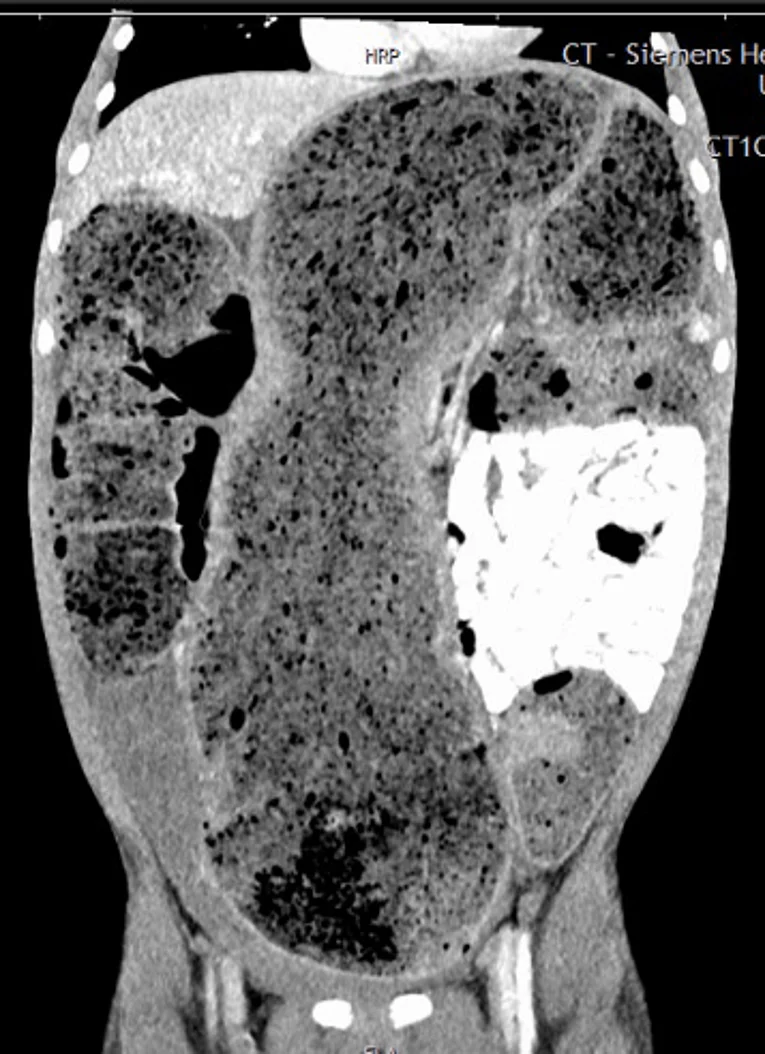

Beim Morbus Hirschsprung handelt es sich um eine angeborene Erkrankung, bei der die Nervenzellen in der Darmwand des Enddarms fehlen. Meistens ist das letzte Drittel des Dickdarms betroffen. Durch die fehlenden Nervenzellen zieht sich der betroffene Darmabschnitt zusammen und führt zu einer Störung des normalen Weitertransports des Stuhlgangs. Der Stuhlgang staut sich vor dem betroffenen Abschnitt an und führt zu einer Aufdehnung des Dickdarms („Megacolon“). Auffällig werden diese Kinder teilweise direkt nach der Geburt durch fehlendes Absetzen des ersten Stuhlgangs („Mekonium“) oder im Säuglings- und Kleinkindalter durch eine chronische Verstopfung. Die Symptome können so stark sein, dass sie einem Darmverschluss ähneln. Eine bakterielle Überwucherung des aufgestauten Stuhlgangs kann zu einem mitunter lebensbedrohlichen Zustand führen („toxisches Megacolon“).